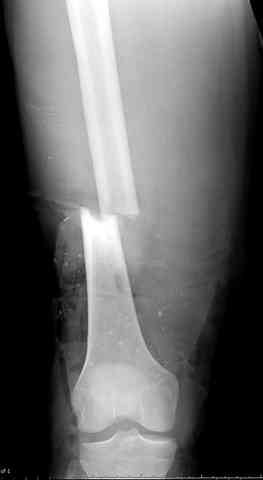

здесь случай с политравмой, перелом зафиксирован  наружным

фиксатором, после третьей irrigation&debridment фиксация бедра

пластиной с последующей кожной пластикой.

Вложение не в текстовом формате было извлечено…

Имя     : 6 open femur, tibia exfix 3.jpg

Тип     : image/jpeg

Размер  : 38730 байтов

Описание: отсутствует

Url     : http://weborto.net:8080/pipermail/ortho/attachments/20080516/ebe5bb74/attachment-0015.jpg